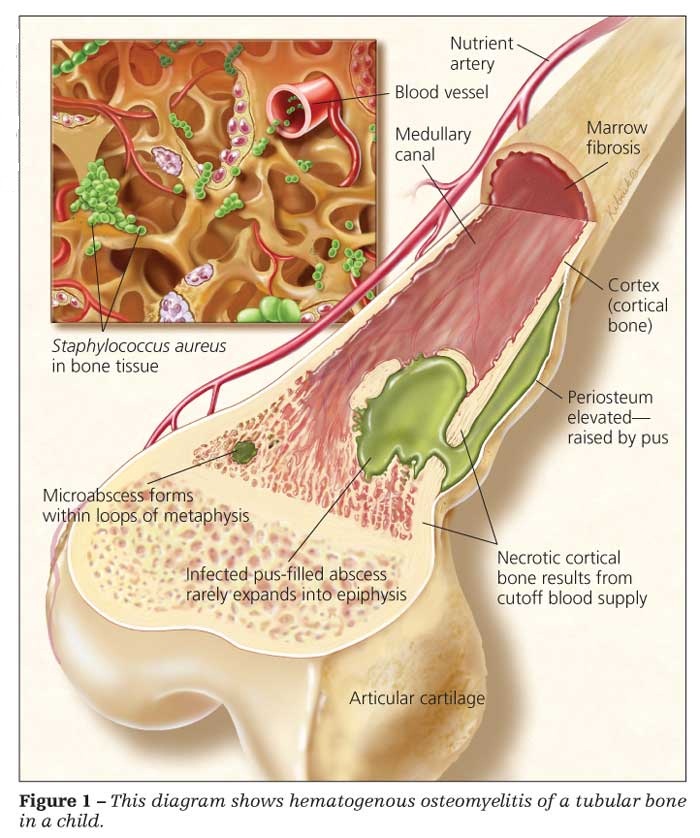

6 Spinal Osteomyelitis Surgery:

There are many of treatments that patients can experience prior having this surgery to correct this spinal infection. Illnesses of the spine are very destructive, and any surgical operations performed on this region lead to risks, as full or partial paralysis.